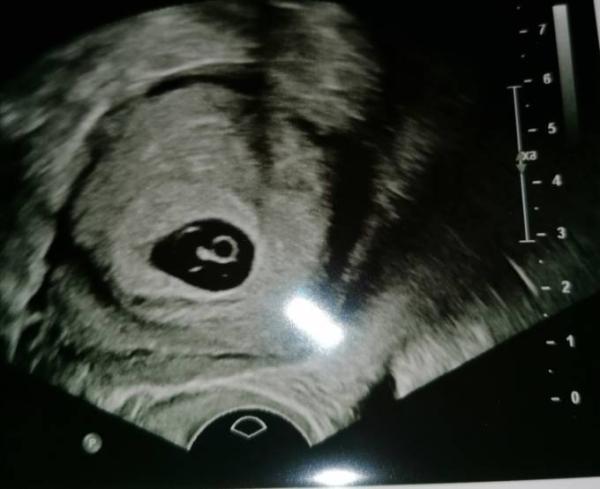

So zweiter Anlauf. Bisher war ich stille Mitleserin, da ich erstmal meinen FA Termin abwarten wollte, soweit so gut, heute war der Termin und naja bin etwas beunruhigt. Wenn ich vom ersten Tag meiner letzten mens ausgehe wäre ich jetz 8+1, nun ist es aber so dass ich laut US erst 6 Woche bin. Kann sich der ES soweit nach hinten verschieben? Oder ist das ein schlechtes Zeichen? Herzschlag war leider auch nicht zu sehen Hab nächste Woche noch mal einen Termin, aber irgendwie hab ich ein komisches Gefühl. P. S. Us Bild anbei

Bild zu Etwas beunruhigt - Forum für Juli - Mamis

Es kann schon gut sein, dass sich mein ES verschoben hat. War bei meinem jüngsten Sohn auch so. Nur muss ich sagen, dass ich da um einiges jünger war und auch nie auf meinen Zyklus geachtet habe, somit unbeschwerter an die Sache gegangen bin. Die Ärztin meinte auch ist ein guter und prall gefüllter dottersack. Aber man macht sich so seine Gedanken. Nächste Woche Donnerstag weiß ich hoffentlich mehr und das positiv. Nein bluttest wurde noch nicht gemacht. Vielen Dank erstmal